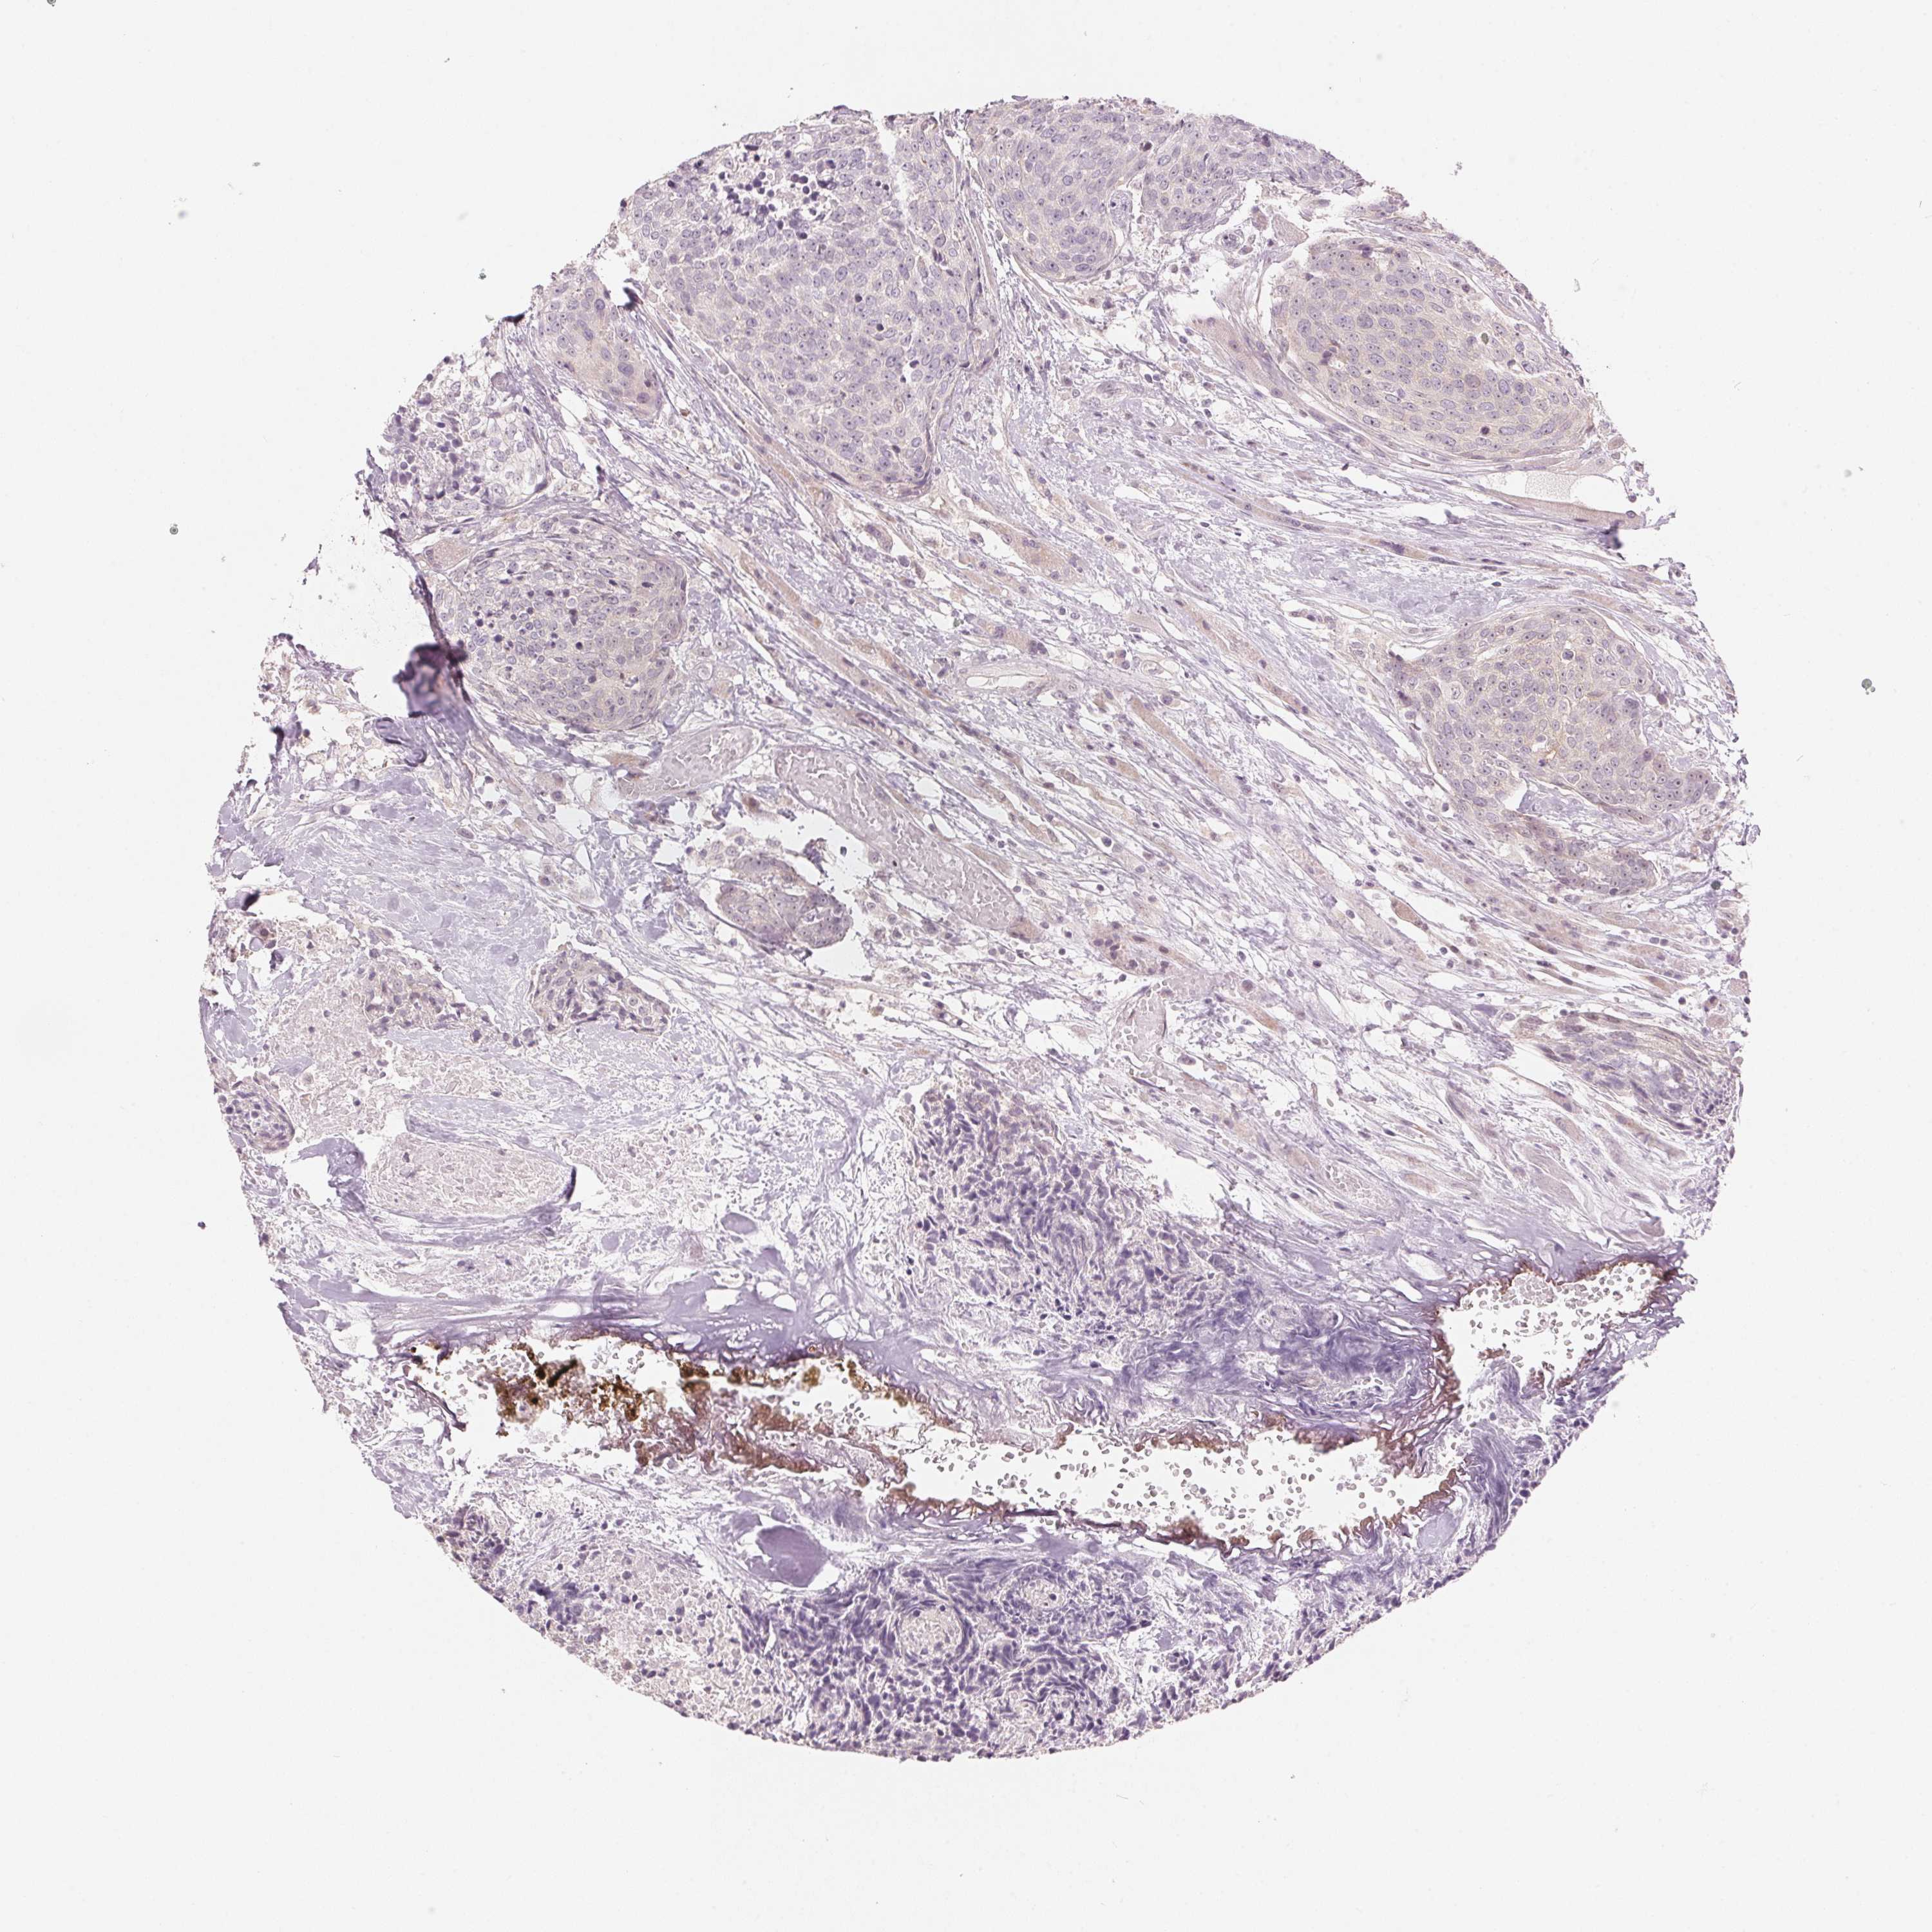

HEAD AND NECK CANCER - Protein expressioni

A mouse-over function shows sample information and annotation data. Click on an image to view it in a full screen mode. Samples can be filtered based on level of antibody staining by selecting one or several of the following categories: high, medium, low and not detected. The assay and annotation is described here.

Antibody stainingi

Antibody staining in the annotated cell types in the current human tissue is reported as not detected, low, medium, or high, based on conventional immunohistochemistry profiling in selected tissues. This score is based on the combination of the staining intensity and fraction of stained cells.

Each image is clickable and will lead to virtual microscopy that enables deeper exploration of all samples and also displays staining intensity scores, fraction scores and subcellular localization as well as patient and tissue information for each sample.

Antibody HPA012532

Staining

High

Medium

Low

Not detected

Intensity

Strong

Moderate

Weak

Negative

Quantity

>75%

75%-25%

<25%

None

Location

Nuclear

Cytoplasmic/membranous

Cytoplasmic/membranous,nuclear

Squamous cell carcinoma, NOS

Adenocarcinoma, NOS